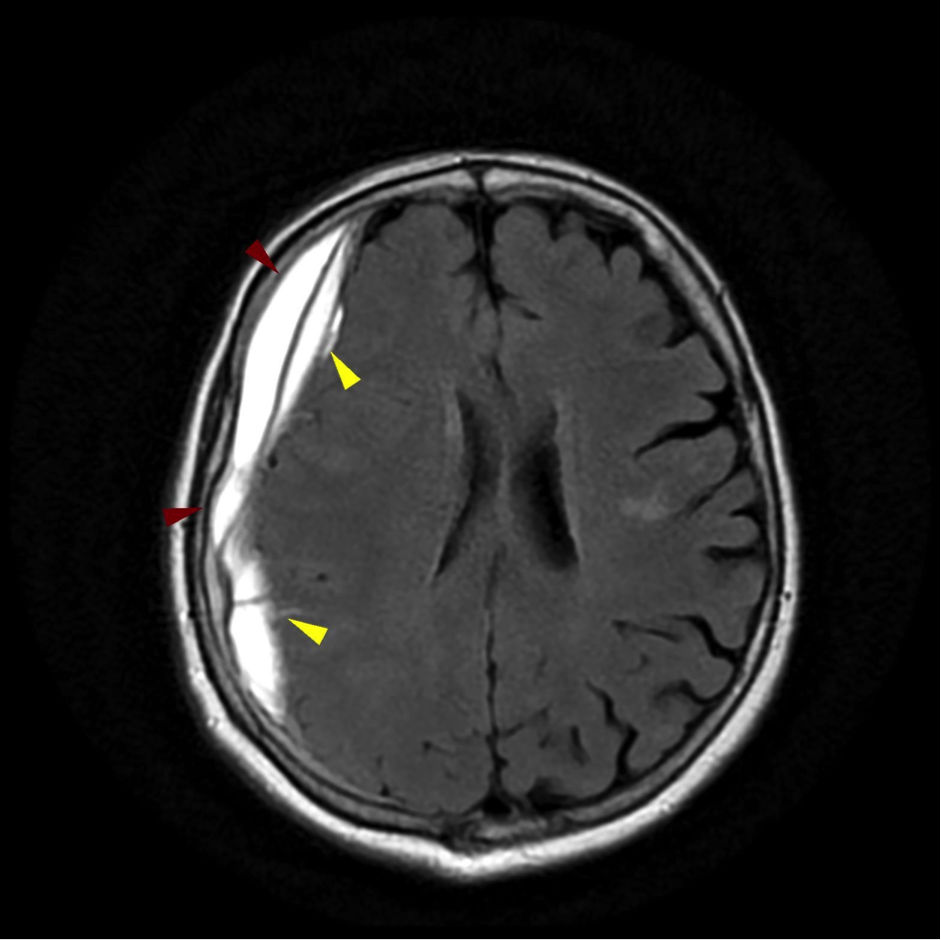

Επισκληρίδιο αιμάτωμα

Το επισκληρίδιο αιμάτωμα είναι αιμορραγία στην περιοχή μεταξύ του κρανίου και της εξωτερικής από τις τρεις προστατευτικές μεμβράνες που περιβάλλουν τον εγκέφαλο (σκληρά μήνιγγα).